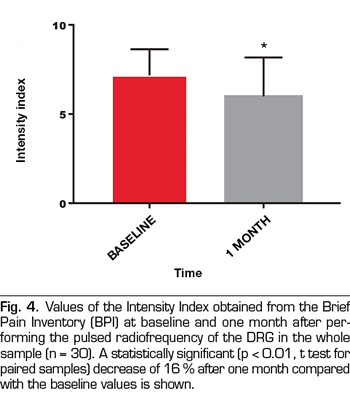

Results: The VNS score decreased from 7.7 ± 2,2 to 5.9 ± 3 (p < 0.01). Intensity and Interference Scores were reduced from 7.1 ± 1.5 to 5.9 ± 2.1 (p < 0.01) and 7.1 ± 1.9 to 6.0 ± 2.3 (p < 0.02) respectively. In 12 patients (40 %) a satisfactory analgesic response was observed. In these patients the VNS decreased from 8.0 ± 1.5 to 3.8 ± 2.6. Intensity and Interference Scores were reduced from 7.4 ± 1.3 to 3.9 ± 1.5 (p < 0.0001) y 7.7 ± 1.9 to 4.9 ± 2,7 (p = 0.002) respectively.

The score in the VNS prior to the procedure was reduced from 7.7 ± 2.2 to 5.9 ± 3 (p <0.01, t test for paired samples), taking into account the entire sample (n = 30), which implies a variation of 23% (Table I, Figure 3). The Intensity Index decreased from 7.1 ± 1.5 to 5.9 ± 2.1 (p <0.01), which implies a change of 16%, while the Interference Index decreased by 15% (7.1 ± 1.9 to 6.0 ± 2.3) (p <0.02) (Table I, Figures 4 and 5). When evaluating the patients who responded favorably using VNS, 12 out of 30 patients showed a decrease of at least 2 points on that scale, representing 40% of the sample. If we analyze these patients separately, we can observe that the initial values of VNS decreased from 8.0 ± 1.5 to 3.8 ± 2.6 after the procedure, which implies a reduction of 53% (Table II, Figure 6).